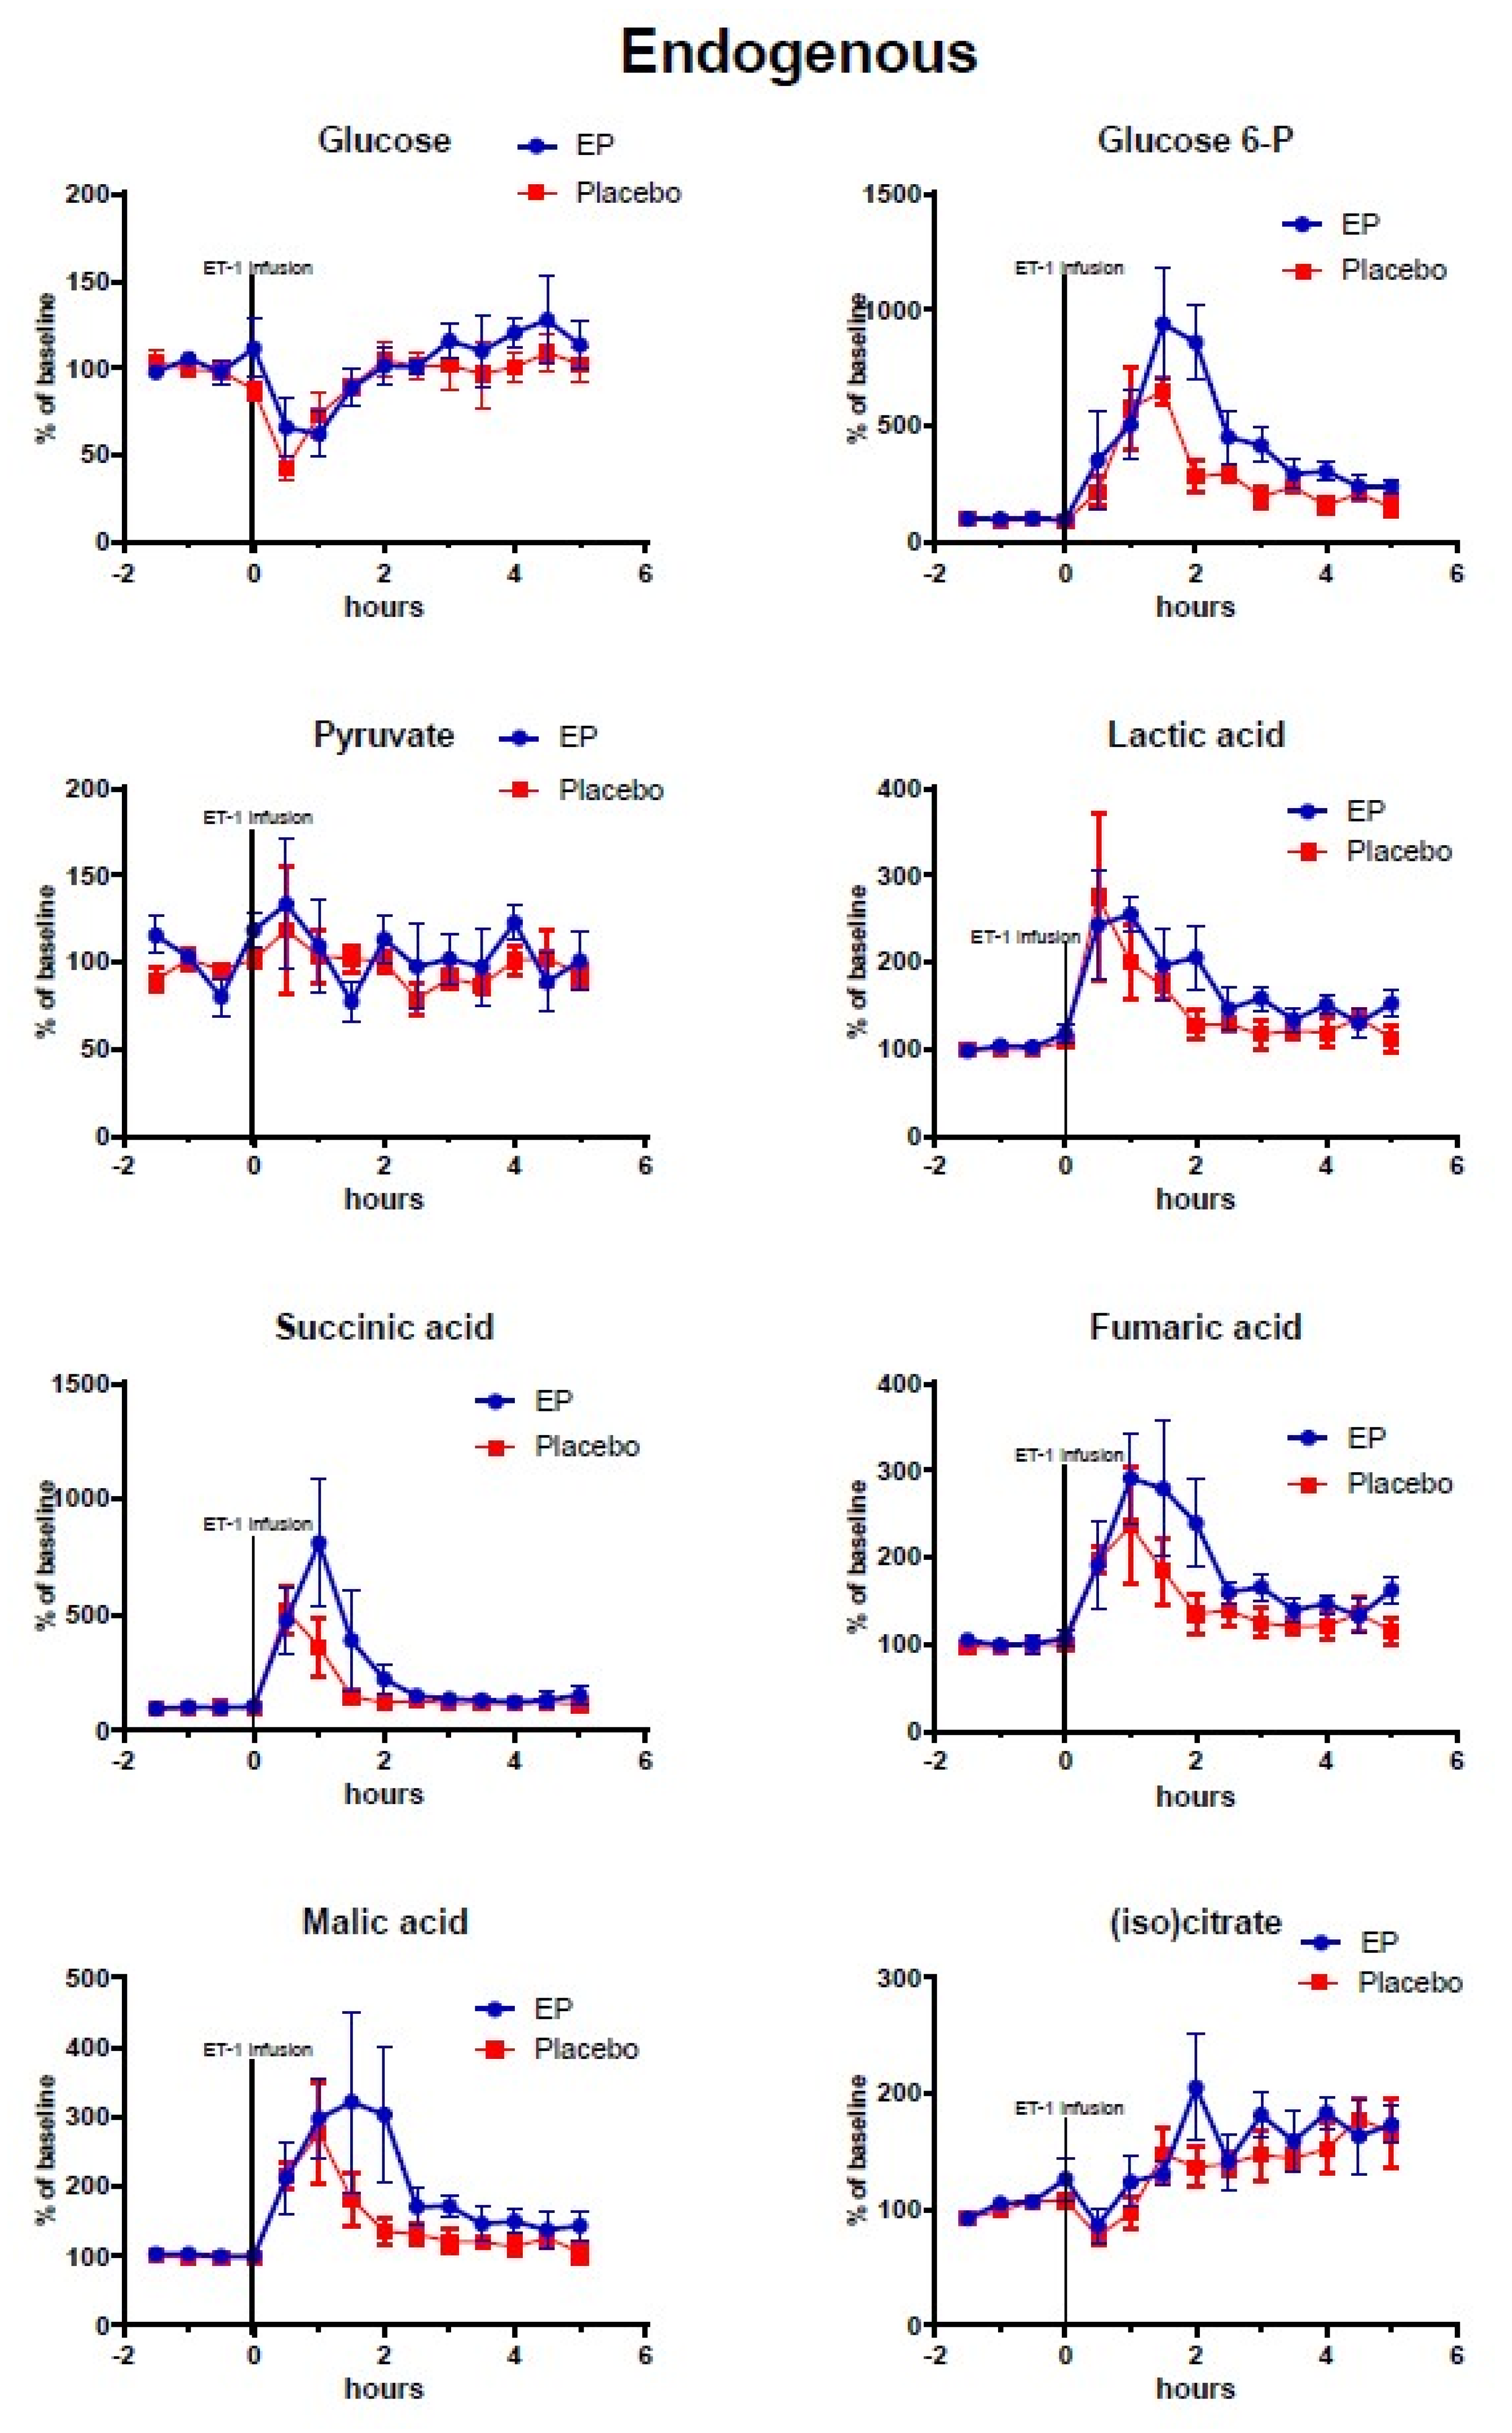

2. Results

2.2. Cerebral Microdialysis